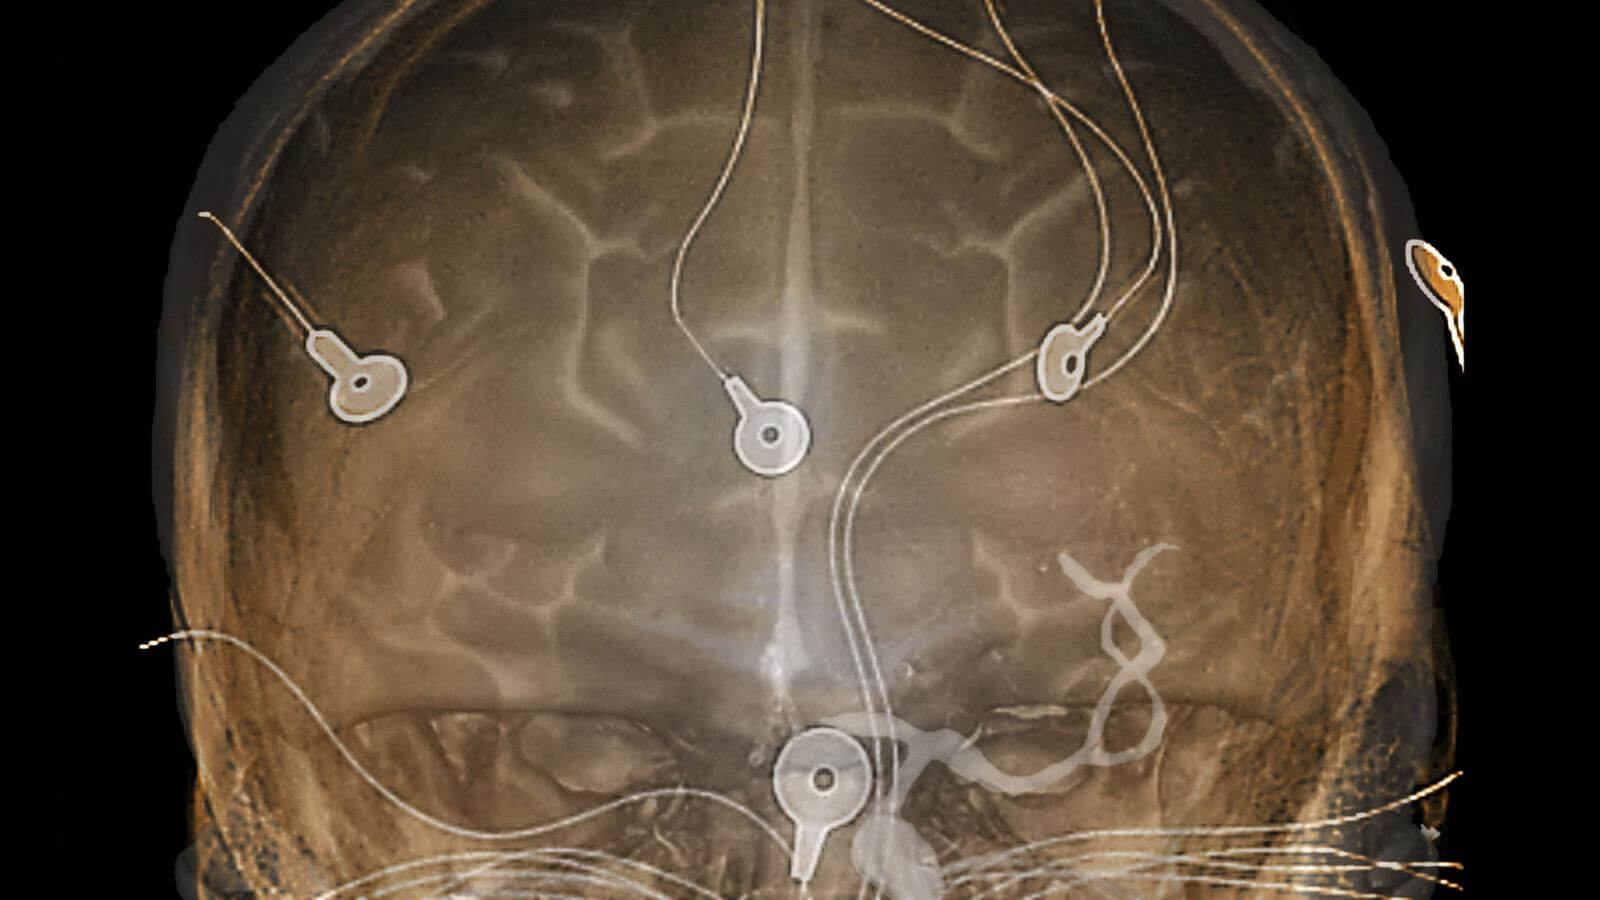

Таким образом, хотя френология была дискредитирована, идея того, что отдельные области мозга могут вызывать определенное поведение, никуда не девалась. Но это не приблизило нас к зрелищу актуальной работы мозга ни на йоту. И только в 1920-х годах ученые научились считывать электрические сигналы мозга. Они впервые взглянули на электрическую активность, которая происходит в мозге живого существа, благодаря технике электроэнцефалографии (ЭЭГ).

Первоначально у нее были весьма странные применения, вроде оценки супружеской совместимости пары или изучения мозгов преступников. Но чаще ее использовали для понимания активности мозга пациентов с эпилепсией, для отслеживания того, что происходит во время припадка.

Поначалу методы были весьма инвазивными. Машины ЭЭГ использовали как для считывания сигналов мозга, так и для стимуляции мозга электричеством. Но одних сигналов мозга было недостаточно, чтобы нарисовать картину мозга. Нужно было что-то новое.